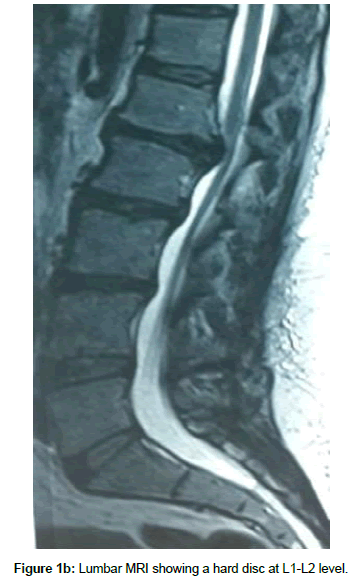

Operation time, the amount of intraoperative blood loss, and the post-operative time to return to routine work and daily life were documented. Clinical and radiological assessments were performed post-operatively and patients were followed up 1, 3 and 12 months after surgery. This follow up included a visiting at an outpatient clinic and telephone interview. As a radiological assessment, all cases had post-operative lumbar x-rays in early post-operative period and in 3, 6 and 12 months after surgery. An independent radiologist made radiographic evaluation based on dynamic lumbar x-rays, 3D CT scans and MRI. Clinical outcomes were collected and graded using the VAS for back and leg pain separately and functional outcomes were measured by ODI scores to quantify the impact of symptoms on patient’s everyday life [12,13]. Figures 1a-1h shows the clinical picture imaging studies and surgical results of three demonstrative patients (Figures 2a-2e and Figures 3a-3d).

Microscopic transforaminal approach was used for all patients. Patients were positioned prone. All pressure points were padded. Then, midline incision was made from one level above to one level below the intended fusion levels. Para spinal muscles were splitted. Under fluoroscopic guidance, bilateral pedicle screws were inserted into L1 and L2. Partial interlaminar L1-L2 laminectomies were done. Unilateral or bilateral resection of the inferior facet of L1 and corresponding pars interarticularis were done Continuation of the procedure differs depending on the consistency of the herniated disc. In the case of hard disc herniations, this was done bilaterally where in the case of soft disc herniation ipsilateral facet -pars removal sufficed. Subsequently, L1 and L2 nerve roots were identified and meticulous hemostasis was obtained with bipolar coagulation of epidural veins and packing veins with hemostatic agents. Now the affected disc space can be easily visualized. If there was a sequestrated fragment, it was dissected softly from the dural sac and removed. This was followed with removal of the remaining contained disc. All steps were done without significant retraction of thecal sac. In the case of the hard calcified discs associated with large osteophyte, the annulus was incised at the extreme lateral side of the disc space and the contained disc material was removed as much as possible, the same scenario was repeated on controlateral side, at this time we aimed to the central part of the calcified disc. Initially, the procedure was started with destruction of L1 caudal osteophyte of tL1 vertebra with the aid of hammering on a boot-like instrument and pushing it into the disc space, The same was done for the osteophyte of L2, Thereafter, the same scenario was repeated on the controlateral side, till the dural sac became free of any compression. Subsequently, the disc space was cleaned from the debris of the broken calcified materials. Then, the rod was assembled on one side and after optimal distraction of the construct and wide opening of the disc space; a peek cage of an appropriate size was inserted into the space from the controlateral side. Of course the floor of the corresponding intervertebral disc space was packed with local bone grafts or demineralized allograft chips prior to insertion of the cage. Finally, the nuts of both constructs were tightened in compression, in order to secure the peek cage. In all these steps, rotating the table and angling the microscope were of great help for visualization of central part of the calcified disc without retracting the dural sac. Wound was closed in anatomical layers. Drain was removed in the first or second post-operative day depending on the amount of the blood drainage.